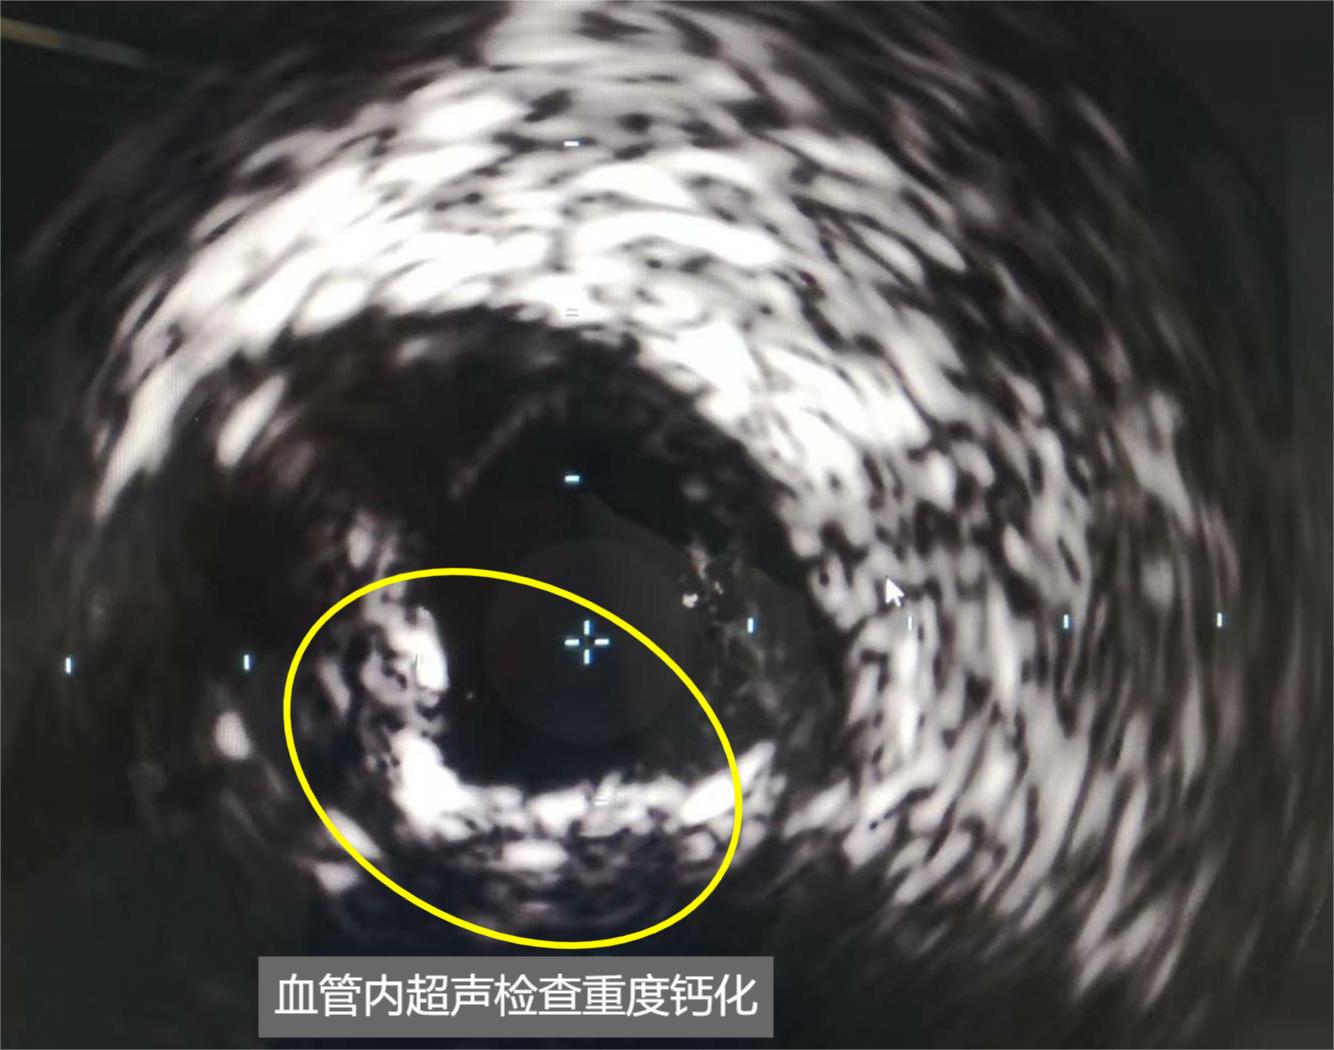

冠脈內超聲(IVUS)檢查顯示馬老先生的血管鈣化嚴重。

冠脈內旋磨術是用導絲將一個前端置有金剛石微粒的橢圓形旋磨頭,送達鈣化血管處。旋磨頭高速旋轉,將鈣化斑塊磨成小于5微米的碎屑。冠脈鈣化,類似于異位的骨結構,有的如戒指環扣在血管內側,有的如鐘乳石懸掛于血管內,影響血流,形成更容易導致血栓的渦流。因其像人體骨骼一樣堅硬無比,與軟斑塊和纖維斑塊可以用球囊擴張擠壓不同,要想疏通阻塞,完成PCI手術,必須使用旋磨技術。

心內科副主任袁蘭所說,心臟介入圈里有句俗話:“天不怕地不怕,就怕冠脈有鈣化。”伴隨著藥物洗脫支架工藝的成熟,術后再狹窄問題已基本解決。醫生對介入治療有了更高的追求,挑戰高難度手術、擴大PCI適用范圍等成為新的目標。冠脈內旋磨術被重新定義為“斑塊修飾”的重要工具。“斑塊修飾”,強調通過旋磨頭打磨鈣化斑塊之后形成新的通道。一方面冠脈內旋磨術開通的管腔,方便后續治療器械通過;另一方面冠脈內旋磨術能有效修飾鈣化病變,有利于支架擴張和貼壁,避免支架內早期血栓的形成。